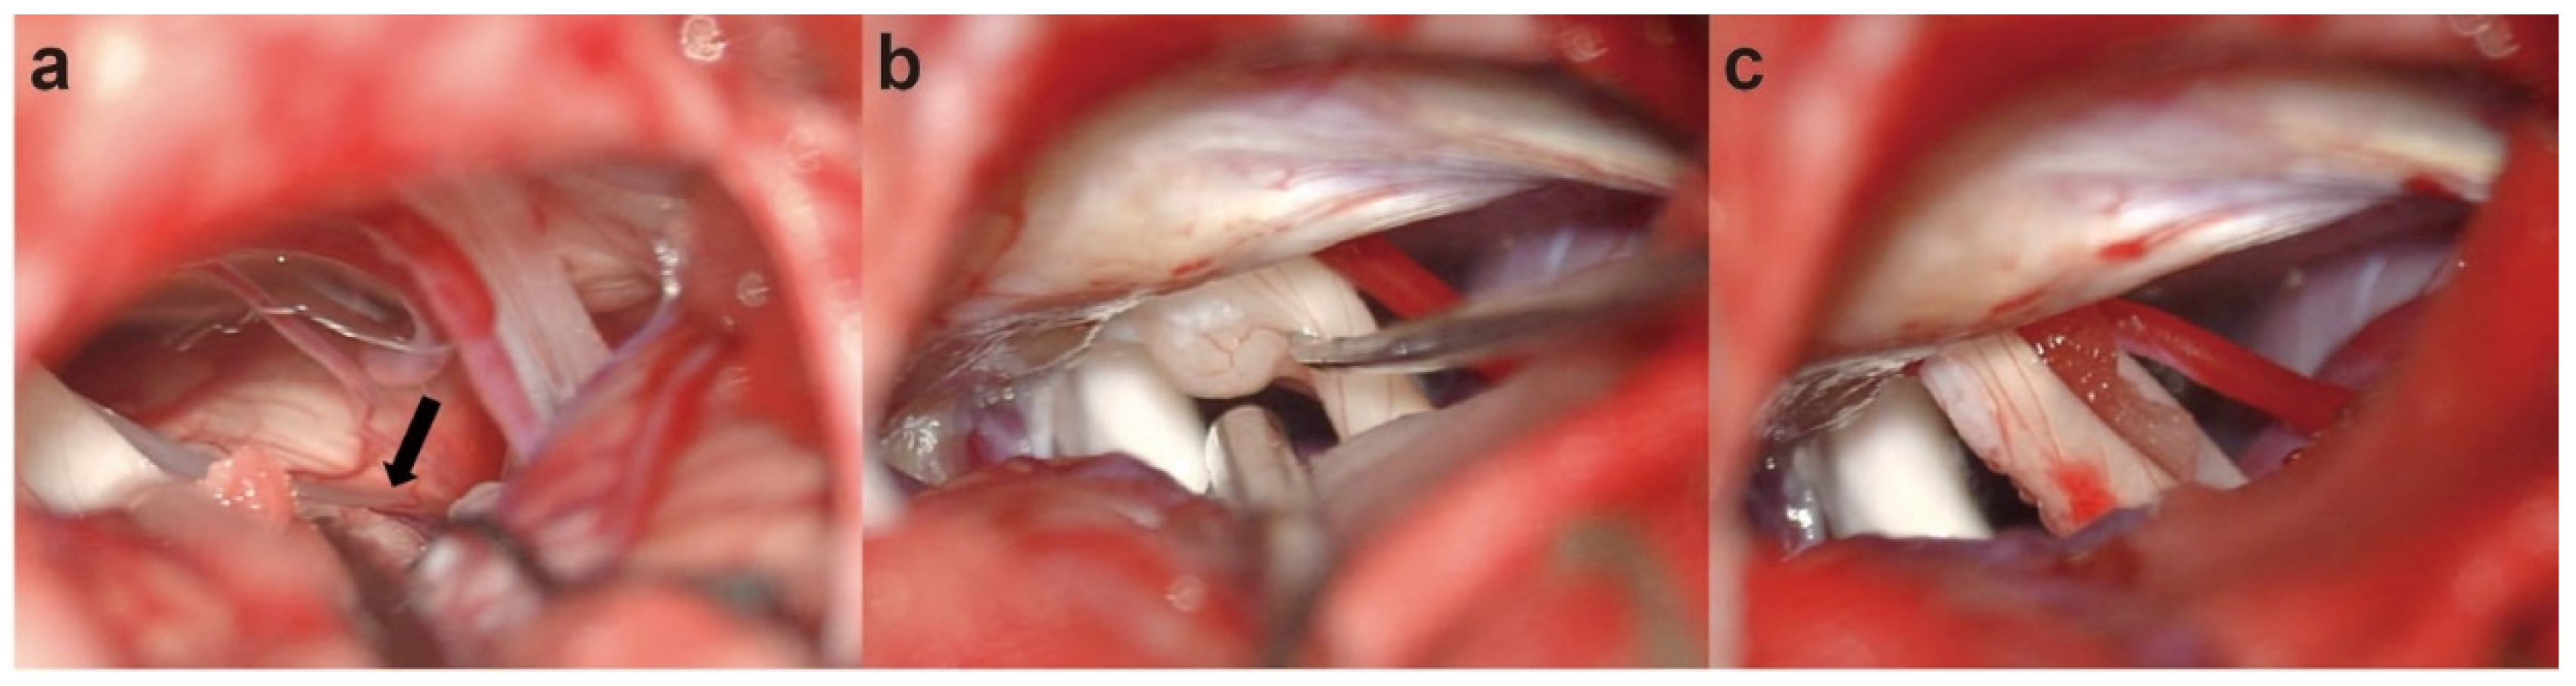

2. Case Report